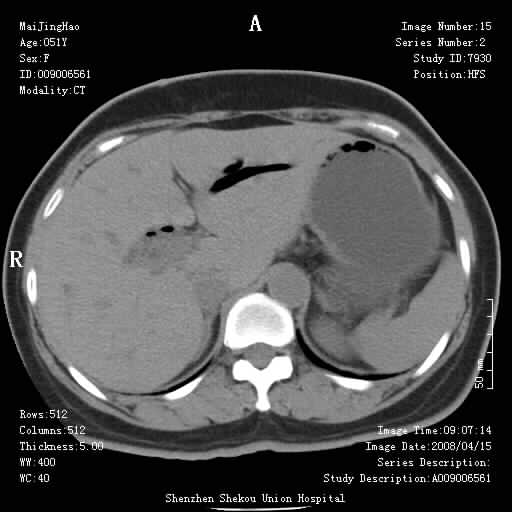

以下是引用余辉在2008-4-26 8:55:00的发言:[br]患者有结石史,此次腹痛4小时,胆总管全程扩张,应有胆总管末端梗阻,此次仍考虑胆结石症,积气不外两种原因,一种是结石下移时肠道内气体逸入,其次为产气菌感染。(倒数第三幅图像于扩张之胆总管末端似可见稍高密度影,考虑为结石影)

以下是引用yangyudong333在2008-4-26 6:17:00的发言:[br]1胆系感染,可能为金葡菌感染,2考虑有化脓性胆管炎致胆总管扩张,3胰头部增大,建议做增强

以下是引用听蝉观竹在2008-4-26 11:41:00的发言:[br]胆道手术分两种情况:[br]1、如果仅仅做胆囊切除手术,肝内胆管不会积气,只会出现胆总管代偿扩张,因为奥迪氏括约肌依然功能正常胆道与外界并不相通;[br][br]2、胆囊切除+胆总管空肠吻合手术(即roux-y式),则肝内胆管会出现积气,只是因为胆管与小肠相通,气体来源于小肠。这是临床十分常见的手术。[br][br]这个病例应该是胆囊切除+胆总管空肠吻合手术,是正常手术后表现,并不是胆道感染的表现。

以下是引用宇宙ct在2008-4-26 10:43:00的发言:[br][br] 胆囊切除术后胆管常因代偿而出现扩张,肝内胆管也经常会出现积气征象;胰头强化后再诊断。 [br] [br]

以下是引用听蝉观竹在2008-4-27 10:10:00的发言:[br]关于胰头大小问题有几种测量方法和正常值:[br][br]1、直量法:横径<4cm;[br]2、胰头横径与相邻层面椎体横径的比值为二分之一,超过椎体横径就提示胰头增大;[br]3、正常组成年人肠系膜上动、静脉水平夹角正常值范围为4.9°~34.7°大于35°提示胰头增大。[br][br]上述方法只是一种具体的判断,是“量”的评估,更重要的是“质”的评估:一是观察边缘是否光滑,有无局部隆起,有无分叶;二是观察密度(增强,尤其在动脉期和门脉期)是否均匀。[br][br]所以对于胰头是否有异常不仅仅是是目测可以解决问题的,不要轻易就说“胰头增大”。还有一个问题就是测量胰头应该在增强ct上进行,这样可以避免将血管测量进去。[br][br]为什么啰嗦讲怎么多,因为我们实际工作中同样存在影像科医生和临床医生动不动就说胰头增大,说是胰头癌。大家看看是不是这种情况?[br][br] 我个人观点-----本病例的胰头不增大。[br][br][本贴已被 听蝉观竹 于 2008-4-27 10:12:41 修改过]